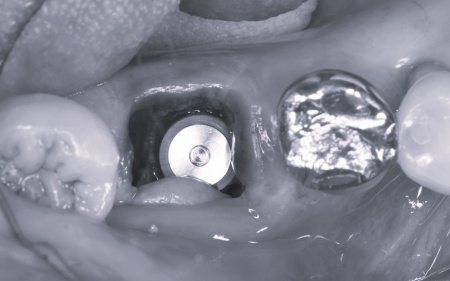

患者様は「できるだけ治療期間を短くしたい」と希望されていることから、右下の第1大臼歯は抜歯即時埋入インプラントを提案しました。 抜歯即時埋入インプラントとは、抜歯と同日に人工歯根「インプラント体」を埋め込む方法です。 これにより、通常のインプラントと比べて治療期間を短縮することができます。 なおこの方法は、骨の量・質・感染の有無・歯ぐきの状態などの条件があり、すべての症例で行えるわけではありません。 また、大臼歯周囲は、歯の周りを保護する硬い歯ぐき「角化歯肉」が不足していました。 手前の小臼歯については「同じ歯の治療を繰り返したくない」とのご希望から、精密補綴治療を提案しました。 それぞれの治療内容を丁寧に説明したところ、すべての治療に同意いただきました。 まず、大臼歯の抜歯から行います。 次に、小臼歯に関しては古い詰め物を取り外し、マイクロスコープを用いて拡大視野のもとで歯の形を整えて型を採り、精度の高いセラミックの被せ物を作製・装着しました。 |